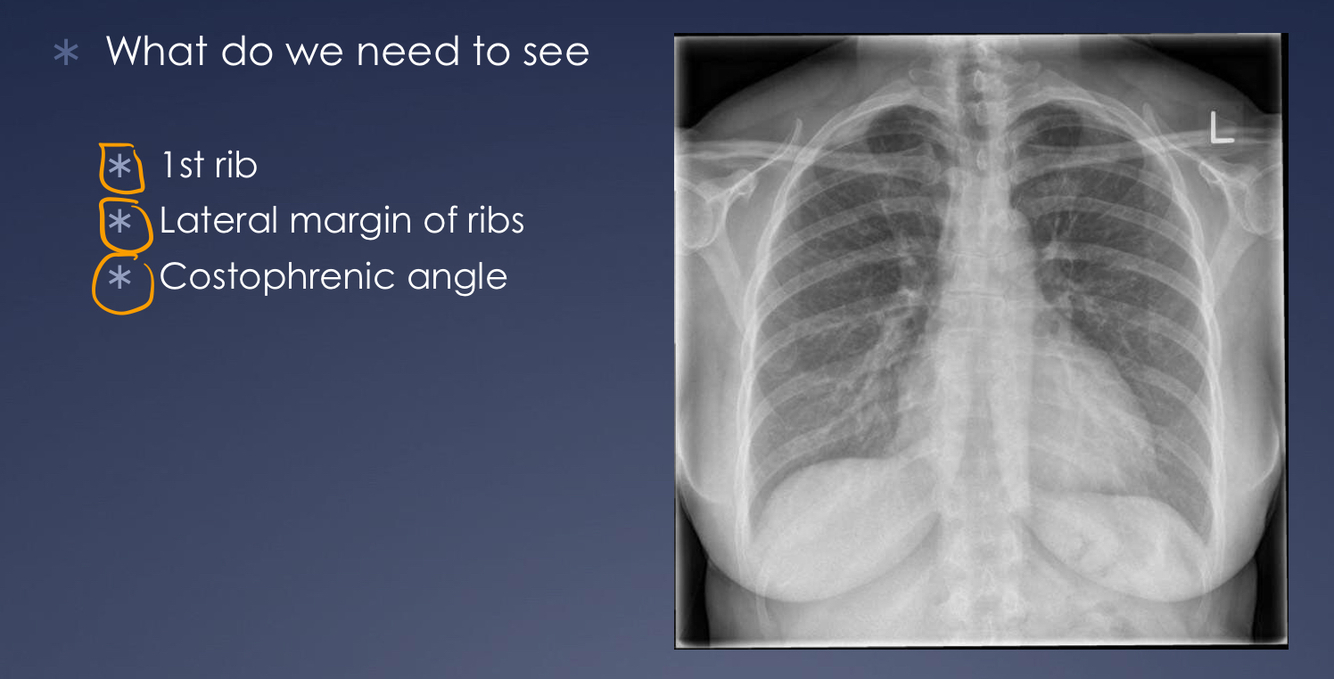

What anatomy should be included in a chest-xray for it to be adequate?

What might be the pathology if the 1st rib is not visible on chest x ray?

Pancoast tumour as it erodes the first rib